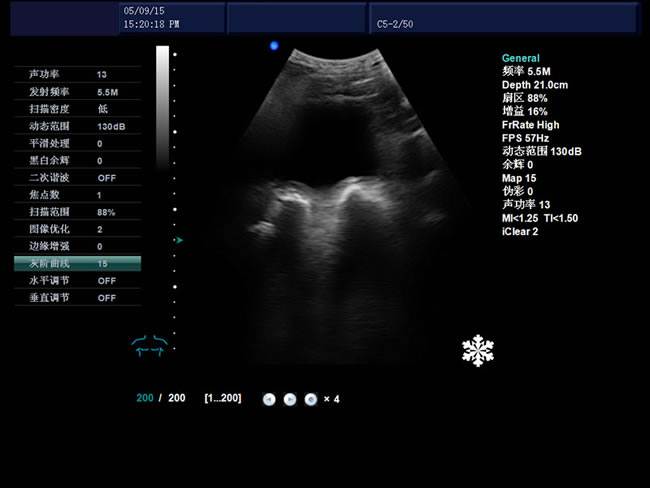

S8 彩色多普勒獸用超聲診斷儀

• S8彩色多普勒獸用超聲診斷儀是徐州市大為電子設備有限公司推出的一款全新的彩色超聲診斷儀器。

探頭信息、顯示模式、深度、焦點、動態范圍、體標、探頭位置標志、聲功率、患者信息、醫療機構名稱、測量值、時間和日期、標尺、掃描方向、灰階曲線、探頭當前工作

頻率、幀頻、B模式總增益、C模式總增益、D模式總增益、菜單、注釋、灰階帶、穿刺引導線、PRF、壁濾波、血流相關、累積次數、TI熱指數、MI機械指數